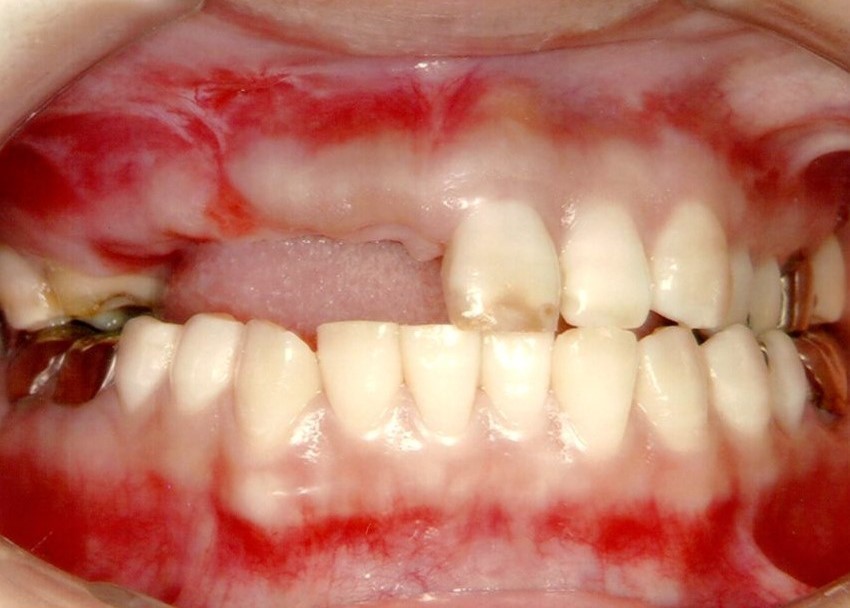

治療前

下の歯は歯周病でグラグラです。

後のインプラント手術時に、抜歯します。